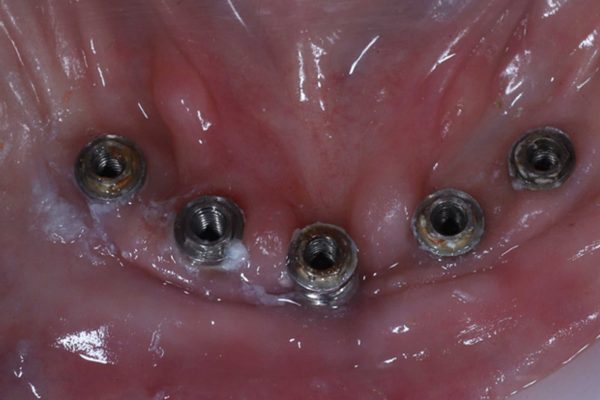

When the implant bridge was off, I was able to irrigate the area and remove the soft plaque deposits present (Figures 5 and 6).

The bridge was replaced, and then the screws torqued down to the manufacturer’s recommendations.